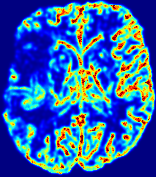

LesionRefer to captionRefer to captionRefer to captionRefer to captionRefer to captionRefer to caption𝐕rgbsubscript𝐕𝑟𝑔𝑏{\bf{V}}_{rgb}Refer to captionRefer to captionRefer to captionRefer to captionRefer to captionRefer to caption𝐕2subscriptnorm𝐕2{\|\bf{V}}\|_{2}Refer to captionRefer to captionRefer to captionRefer to captionRefer to captionRefer to captionRefer to caption3.53.53.52.82.82.82.12.12.11.41.41.40.70.70.70.00.00.0(mm/s)𝑚𝑚𝑠(mm/s)D𝐷DRefer to captionRefer to captionRefer to captionRefer to captionRefer to captionRefer to captionRefer to caption0.0200.0200.0200.0160.0160.0160.0120.0120.0120.0080.0080.0080.0040.0040.0040.0000.0000.000(mm2/s)𝑚superscript𝑚2𝑠(mm^{2}/s)Slice #1Slice #2Slice #3Slice #4Slice #5Slice #6

Figure 4: PIANO feature maps for another patient in the ISLES 2017 training set, where the lesion is located in the right hemisphere. Top row: segmented stroke lesion region (white) on different slices. The corresponding slices for the PIANO feature maps are shown in the following rows.

For a better insight into an estimated velocity field 𝐕𝐕{\bf{V}} and diffusion field 𝐃𝐃{\bf{D}}, we compute the following maps: (1) 𝐕rgbsubscript𝐕𝑟𝑔𝑏{\bf{V}}_{rgb}: Color-coded orientation map of 𝐕=(Vx,Vy,Vz)T𝐕superscriptsuperscript𝑉𝑥superscript𝑉𝑦superscript𝑉𝑧𝑇{\bf{V}}=(V^{x},V^{y},V^{z})^{T}, obtained by normalizing 𝐕𝐕{\bf{V}} to unit length and mapping its 3 components to red, green, blue respectively; (2) 𝐕2subscriptnorm𝐕2\|{\bf{V}}\|_{2}: 222 norm of 𝐕𝐕{\bf{V}}; (3) D𝐷D: scalar field in Eq. 5.

Fig. 3 and Fig. 4 show the PIANO feature maps estimated from two ISLES 2017 patients: all are highly consistent with the lesion in both cases. Details of the blood flow trajectories are revealed in 𝐕rgbsubscript𝐕𝑟𝑔𝑏{\bf{V}}_{rgb} by the ridged patterns and the sharp changes of colors in the unaffected (right) hemisphere, while the flat patterns appearing within the lesion provide little directional information about the velocity and indicate low velocity magnitudes. Velocity magnitudes are more directly visualized via 𝐕2subscriptnorm𝐕2\|{\bf{V}}\|_{2}, from which one can easily locate the lesion where 𝐕2subscriptnorm𝐕2\|{\bf{V}}\|_{2} is low. D𝐷D also indicates lower diffusion values in the lesion, though with less contrast potentially due to the fact that it captures the accumulated effect of CA diffusion at the voxel-level.